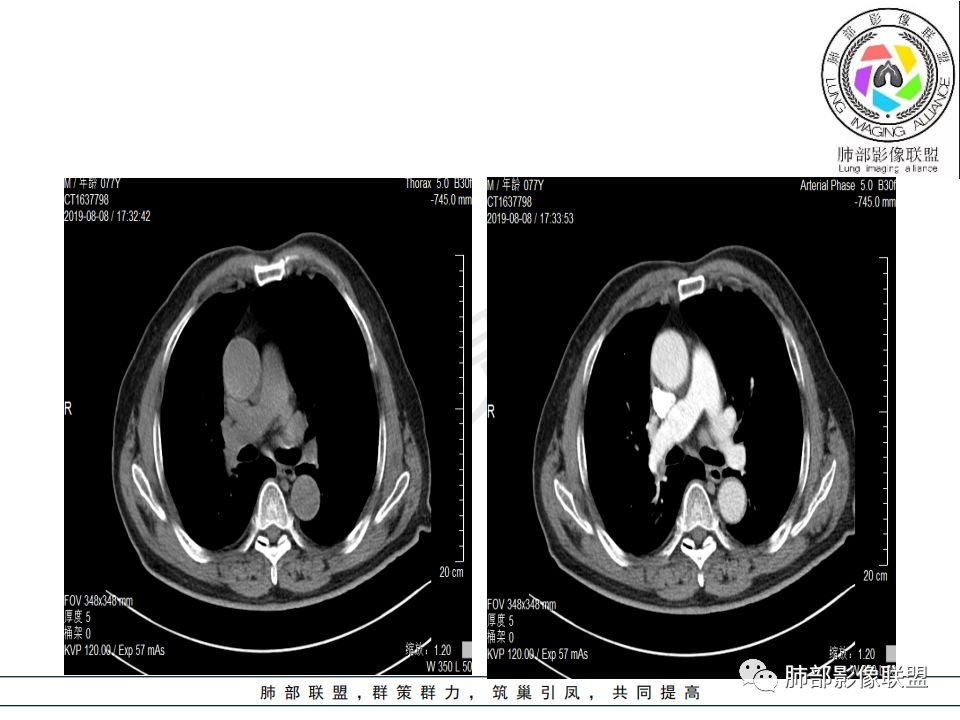

右肺主支气管有软组织肿块,向腔内外生长,右肺上叶肺不张,边缘光滑,增强扫描不均匀强化。考虑恶性肿瘤,鳞癌可能。

晨读,右肺主支气管有阻塞,腔内.腔外都见软组织影,右肺上叶不张,肿块内部密度不均匀,是不是有坏死影,老年男性,考虑恶性~鳞癌

影像:影像右侧大支气管阻塞,临床没有症状或很轻微,要想到胃腺癌转移;胸壁代偿好,透亮度稍低不明显,慢性过程;34.8-52.5HU,主病灶支气管前壁另有1结节,都做成增强两期了,动脉期较平扫有强化;

晨读:患者老年男性,以咳嗽一月就诊,少量白痰,胸CT:纵隔右移,右肺体积缩小,气管下段管壁可见结节样改变,气管软骨变形,气管下段及右主支气管可见新生物向管壁浸润,并向管腔外生长,右上肺肺不张,但不张边缘可见病灶呈膨胀性生长,可见分叶,增强后强化明显。考虑:肺部恶性病变(鳞癌?)

右肺上叶肿块,边缘光滑,略膨隆,近段支气管堵塞,平扫密度均匀,增强后不均匀强化,其内可见不规则血管和坏死,纵隔淋巴结肿大,老年男性,无感染性病史,综合考虑恶性肿瘤(鳞癌,腺癌),鉴别:OP(一般下叶多见)

从强化情况和冠状位看主要还是从外向内的一个肿块,有不张,但不张范围不大,近端支气管堵塞,考虑腺癌或类癌(原发或转移都可能),鉴别鳞癌。

1.右肺上叶较大块影,密度不均,轻度强化并见低密度区,所属支气管截断并腔内突入,是符合肺鳞癌的影像学特征和生物学行为的。